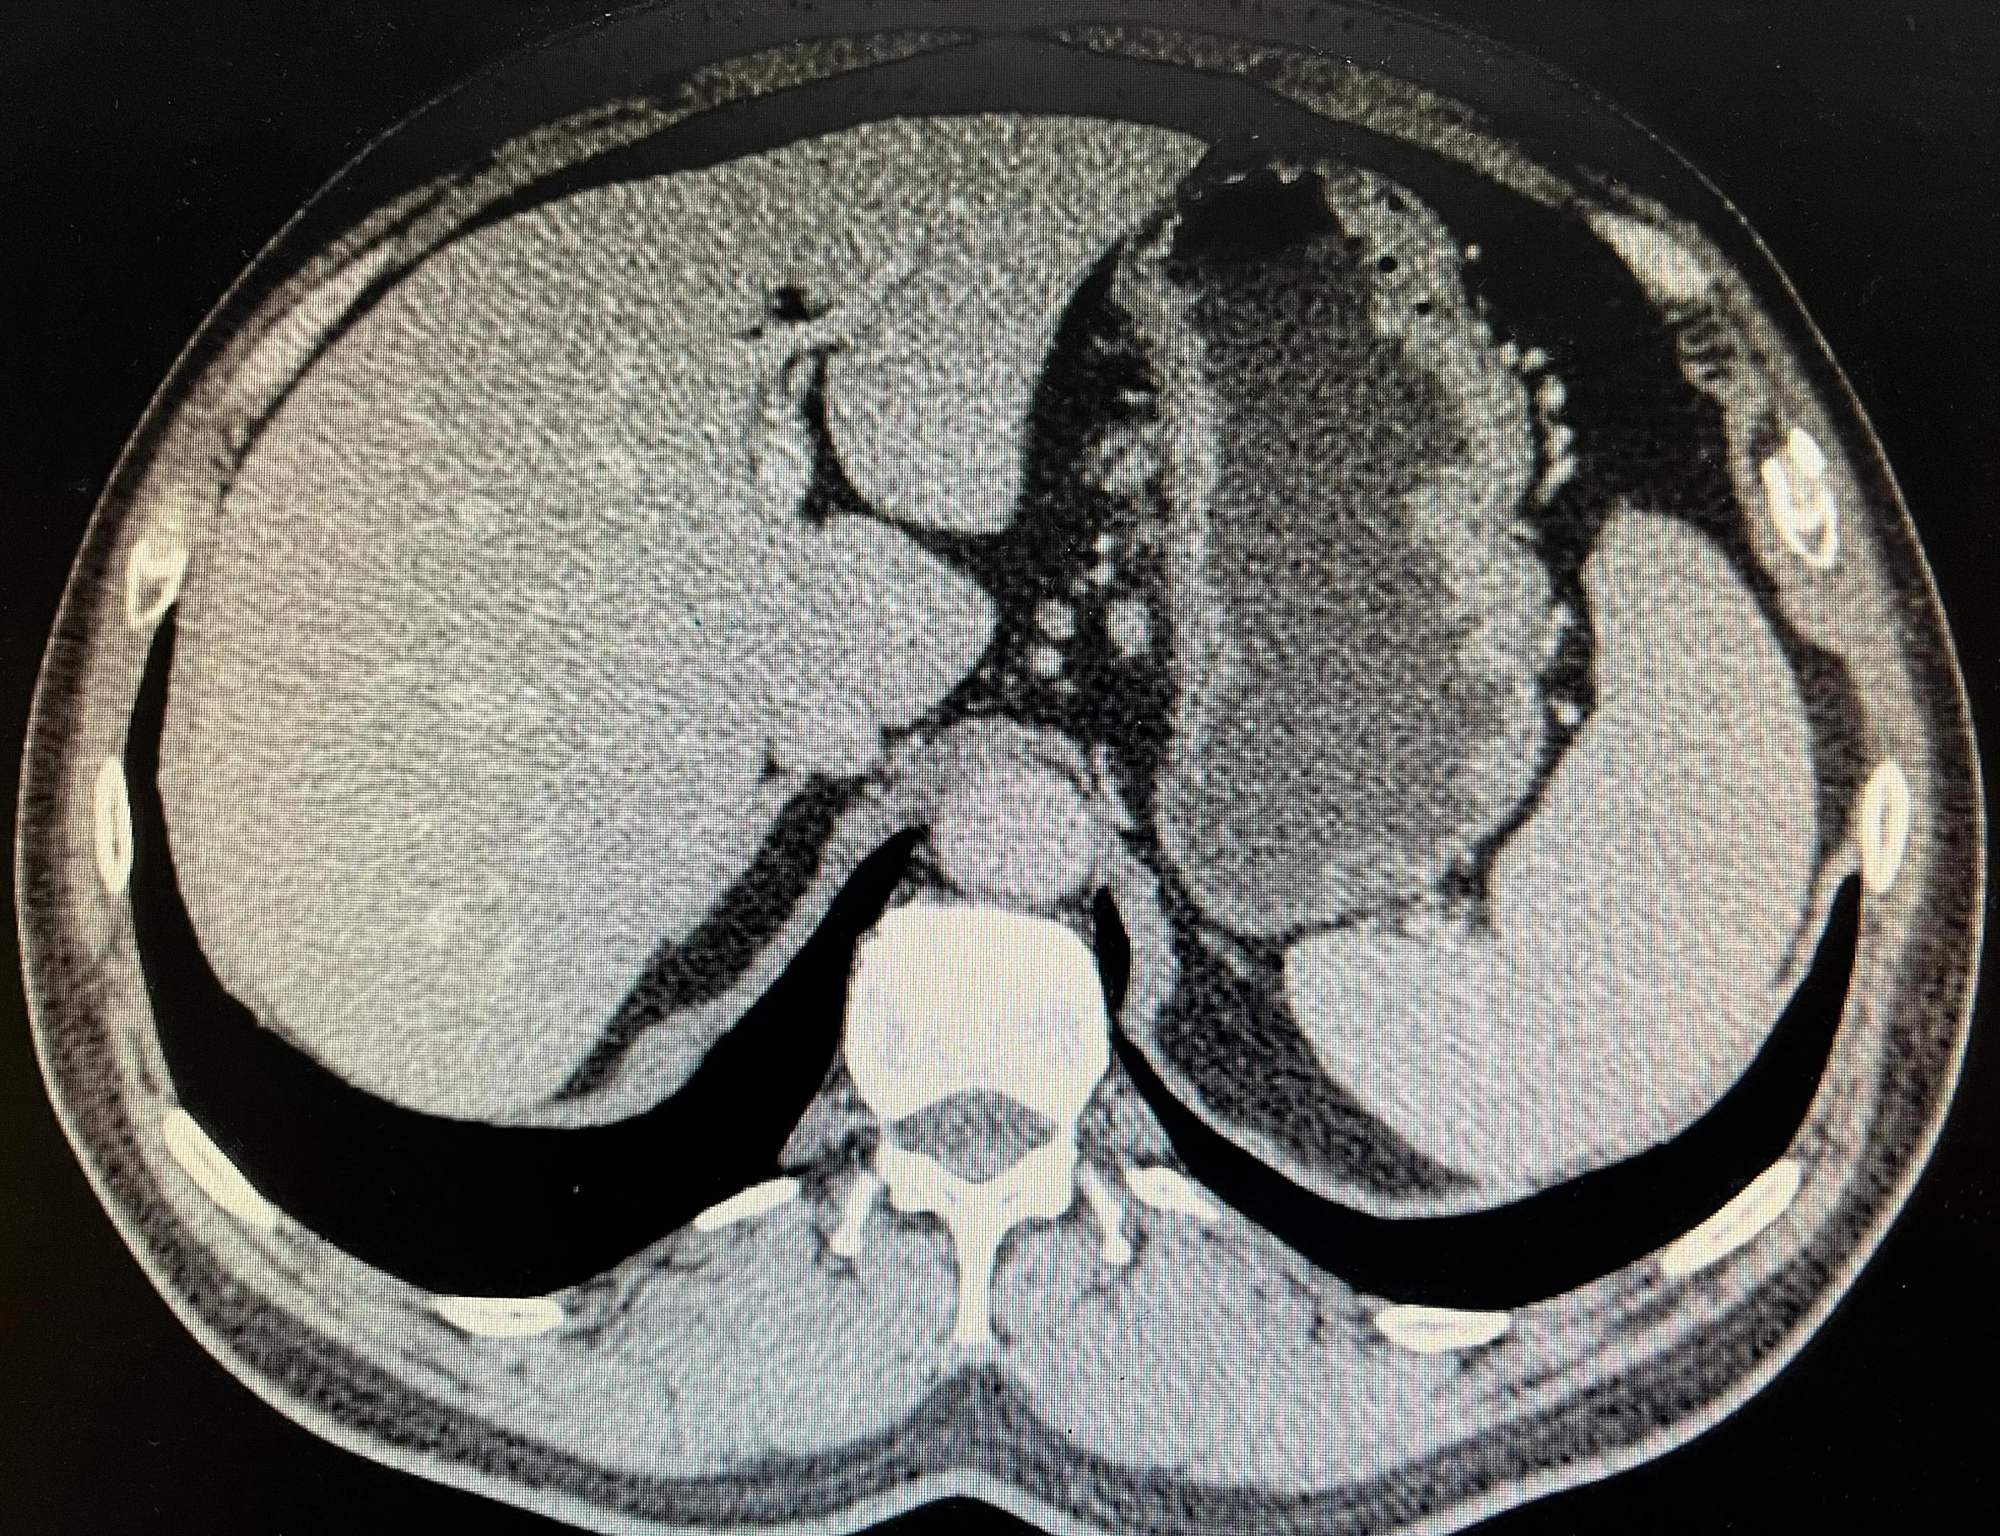

食管下段贲门胃底癌一例